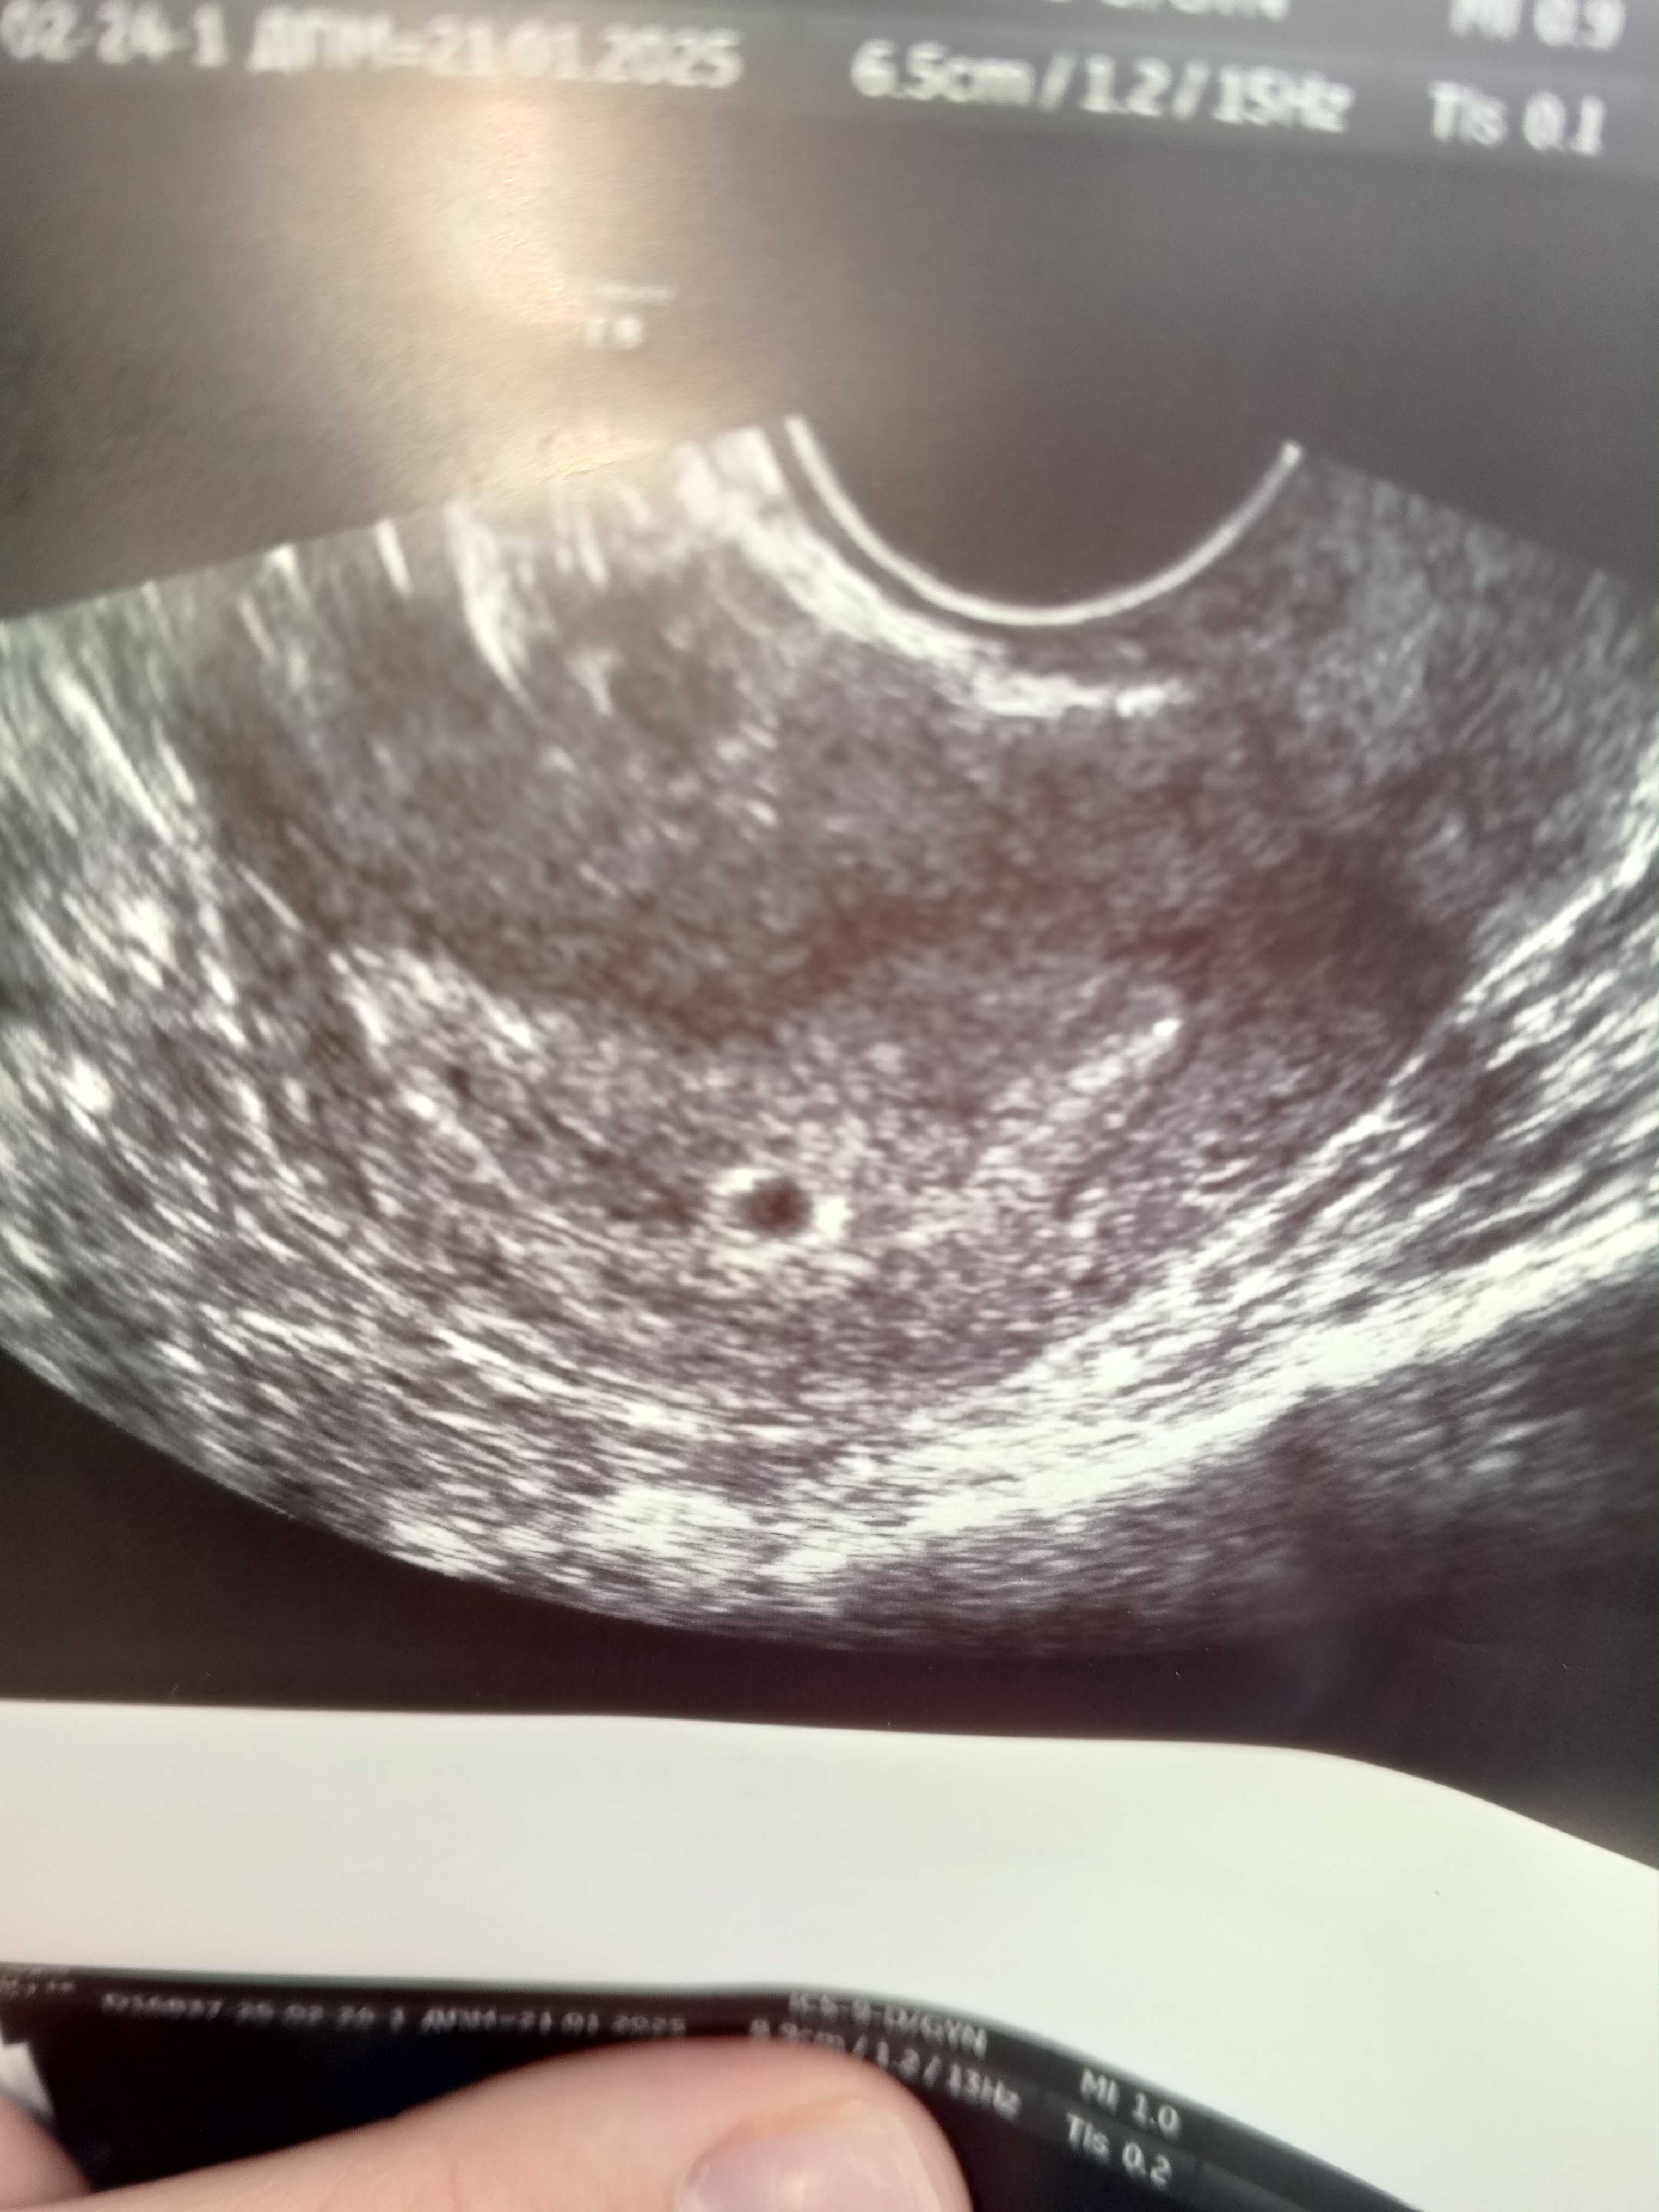

У нас получилось! Я беременна!

4нед 6 дней по месячным

Для нас сейчас самое главное, что беременность маточная. Держись, сюрпризик, мы тебя очень ждём 🤗